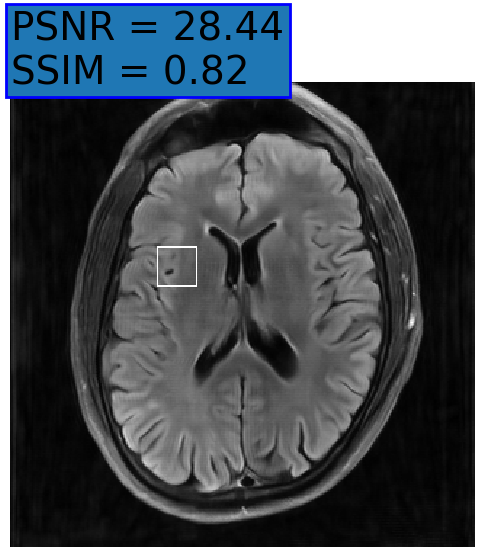

Figure 3: Reconstructions results. Rows 1 and 3: Examples of comparing the ground truth (GT) fully sampled image to the reconstructed images obtained by the three models (1-3), NPB-REC, baseline, E2E-VarNet trained with Dropout, and the NPB-REC std. map at accelerations R=4𝑅4R=4, R=8𝑅8R=8, respectively. Rows 2 and 4: The corresponding annotated ROIS of Nonspecific white matter lesions.

Fig. 3 presents examples of reconstruction results obtained by (1) our NPB-REC approach, (2) the baseline, and (3) Monte Carlo Dropout, for equispaced masks with two different acceleration rates R=4𝑅4R=4 and R=8𝑅8R=8. The reconstructed images predicted by the three models are smoother than the reference image. This is due to the fact that all the models were trained with SSIM loss, which tends to produce overly smooth reconstructions while preserving the diagnostic content and the anatomical features Sriram et al. (2020a). These images can be enhanced by dithering the image by adding a small amount of random Gaussian noise to produce a more textured reconstruction, as proposed in Sriram et al. (2020b).

Table 1 presents the mean PSNR and SSIM metrics, calculated over the whole inference set, for the three models. Our NPB-REC approach achieved significant improvements over the other methods in terms of PSNR and SSIM (Wilcoxon signed-rank test, pmuch-less-than\ll1e-4, except for SSIM values in line W, R=4𝑅4R=4 where they are roughly the same for NPB-REC and Baseline). The improvement in the reconstruction performance can be noted both quantitatively from the metrics, especially for masks with acceleration rate R=8𝑅8R=8, and qualitatively via the images of annotations, where our results show less smoothness than those obtained by Dropout.